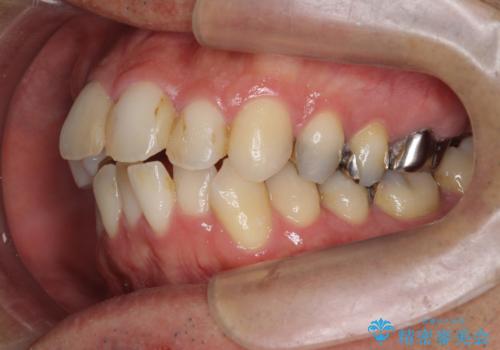

矯正と虫歯のセラミック治療 総合歯科治療の実践

- 突き出た前歯の角度の改善と虫歯治療の改善を求めて来院されました。

虫歯を除去したのち、マウスピース矯正治療を行い、歯並びやがたつきを改善したのち、セラミックに置き換えることで審美性の向上を計画します。